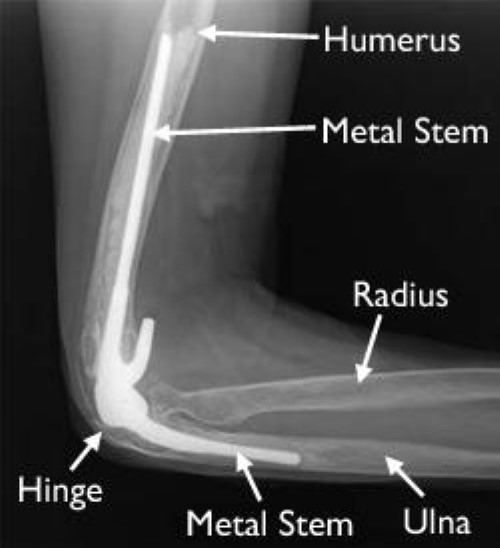

An x-ray of a total elbow replacement

An X-ray of a total elbow replacement taken from the side.

Reproduced with permission from Sanchez-Sotelo J, Ramsey M, King G, Morrey B. Elbow Arthroplasty: Lessons Learned From the Past and Directions for the Future. Instr Course Lect 2011; 60:157-169.

In total elbow replacement surgery, the damaged parts of the humerus and ulna are replaced with artificial components. The artificial elbow joint is made up of a metal and plastic hinge with two metal stems. The stems fit inside the hollow part of the bone called the canal.

The replacement stems are placed into the humerus and ulna bones and kept in place with a bone cement. The two stems are connected by a hinge pin.